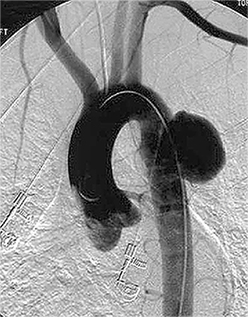

Ендоваскулярна операція - встановлення стент-графту

аневризма аорти

Рисунок 4. Ендопротезування аорти:

А - виведення стент-графту,

Б - стент-графт розправлено

Сенс втручання в ізолюванні мішка аневризми від кровотоку спеціальним пристроєм - стент-графтом. При цьому кровотік залишається всередині стент-графта, а порожнину аневризми, що знаходиться між зовнішньою поверхнею стент-графта і зміненою стінкою аорти, виключають із кровотоку. Це призводить до тромбозу порожнини аневризми (кров, що перебуває без руху, самостійно тромбується через короткий проміжок часу) з подальшим заміщенням сполучною тканиною.

Стент-графт - поєднання судинного ендопротеза зі стентом, являє собою трубку з ПТФЕ (політетрафторетилен), яку утримує в розкритому стані складний дротяний каркас, що нагадує пружний стент великого діаметра. Як і судинний протез, стент-графт може бути лінійним або біфуркаційним (конструкція, що за формою нагадує штани). У складеному стані стент-графт уміщається в трубку відносно невеликого діаметра, а в розкритому стані - повинен максимально відповідати незміненим ділянкам артерій, до яких прилягає. Підбір або виготовлення стент-графта здійснюється суто індивідуально згідно з даними комп'ютерної томографії або інших досліджень, що дають змогу індивідуально змоделювати ділянку аорти, що підлягає втручанню.

Хід операції: ендоваскулярний хірург через невеликий розріз стегнової артерії (частіше правої) вводить в аорту систему доставки - трубку зі стент-графтом у складеному стані. Під рентгенконтролем стент-графт максимально точно підводять до ділянки аневризми і розкривають таким чином, щоб обидва кінці графта щільно прилягали до незмінених ділянок аорти, забезпечуючи повну герметизацію мішка аневризми. Систему доставки видаляють, розріз артерії та шкіру зашивають.

За необхідності ізолювати не тільки аорту, а й змінені клубові артерії (а така необхідність виникає за більшості аневризм черевної аорти), використовують біфуркаційний стент-графт. Методика його встановлення дещо складніша і потребує хірургічного мінідоступу як до лівої, так і до правої стегнових артерій.